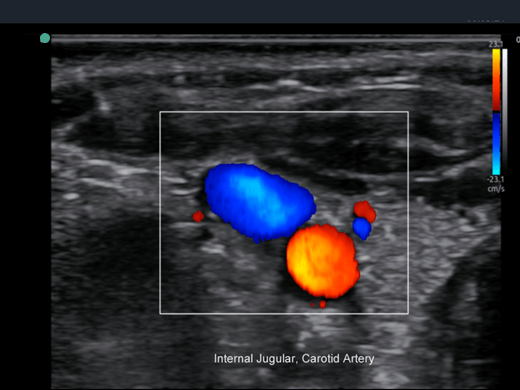

Invictus E5

O ultrassom Invictus E5 apresenta um design moderno e exclusivo, com perfeito fluxo de trabalho e interface intuitiva.

Dentre suas características inovadoras, podemos destacar a tela em LCD com rotação de 60° para ambos os lados, para otimização da visualização durante os exames; tela touch screen com menu totalmente customizável; painel de controle totalmente selado para facilitar limpeza e desinfecção da superfície, o que o torna referência para ser utilizado principalmente em Centro Cirúrgico.

Apresenta excelente qualidade de imagem, trabalho otimizado através de presets pré-determinados, sensibilidade e eficiência em aplicações de Point of Care e portanto, uma perfeita relação custo benefício.